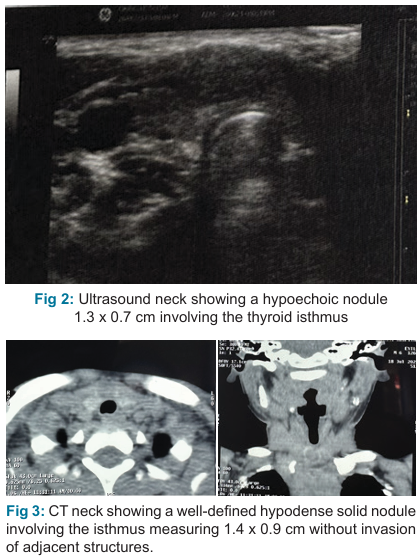

We report a case of papillary thyroid carcinoma in a 6-year-old male child who presented with a solitary midline thyroid nodule initially diagnosed as adenomatous goiter on fine needle aspiration cytology. Our case highlights the need for careful preoperative workup, management and follow-up of such cases in the pediatric age group.